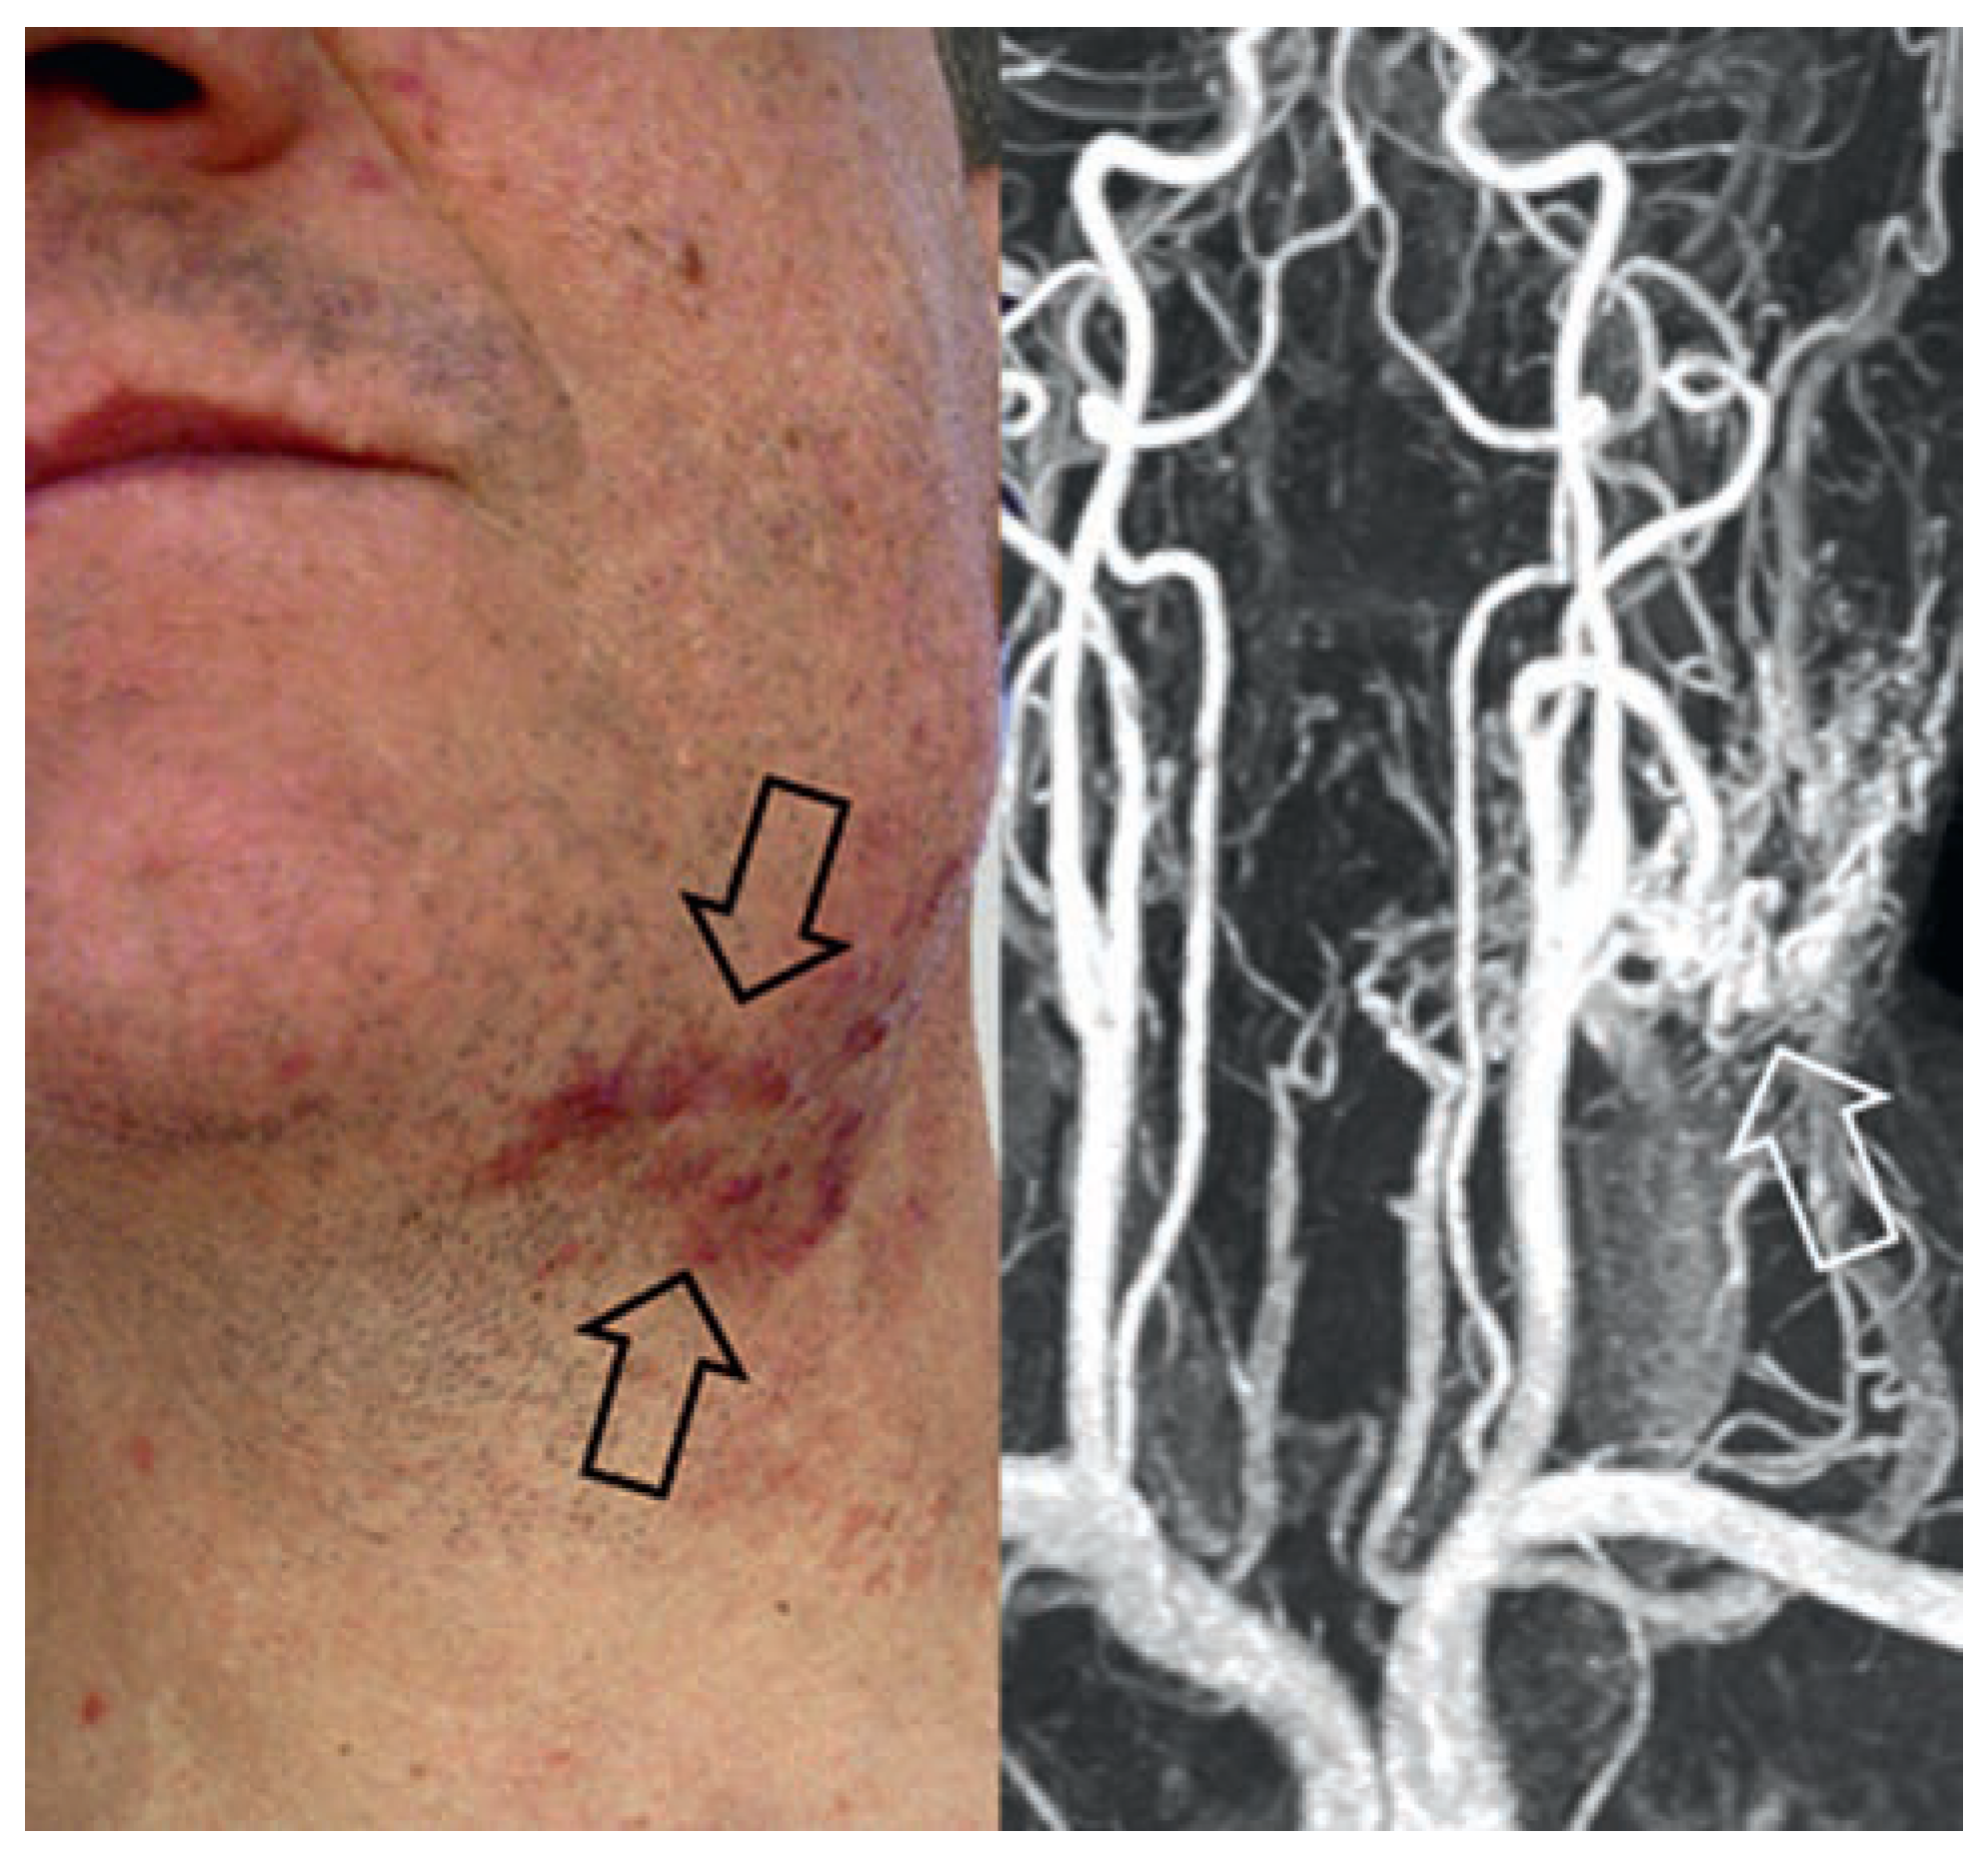

Arterielle Malformation und arteriovenöse Fistel